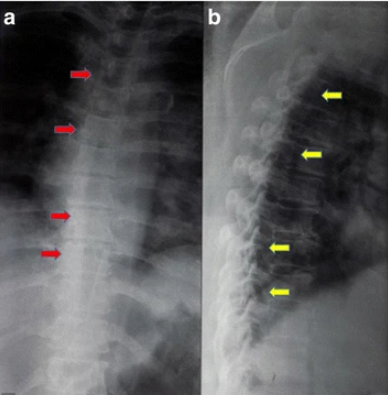

進行了胸部X光檢查,結(jié)果正常(見圖1)。T1加強磁共振成像顯示,Th8和Th9椎體后方硬膜內(nèi)位置有一個規(guī)律性的低強度病變,主要位于左側(cè)。該病變壓迫了脊髓向左。在T2加強磁共振成像中,病變相對于正常脊髓具有等強度(圖2)。

1 胸腔區(qū)域、前后側(cè)和側(cè)面的普通X光片。a 前后視角顯示脊柱畸形及胸椎周圍的腫塊沉積過程(紅色箭頭)。b 側(cè)面圖顯示脊柱管某一水平處有退行性腫瘤沉積(黃色箭頭))